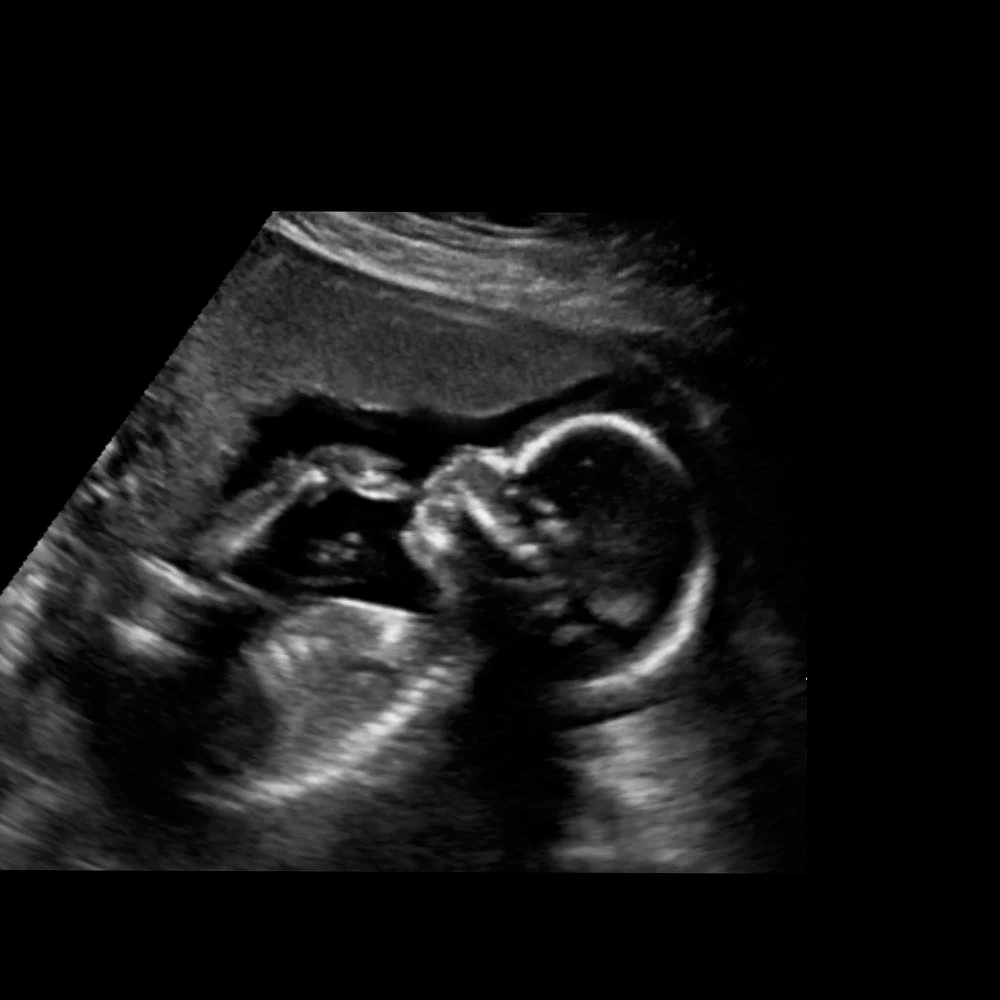

Неделя № 12

Копчиково-теменной размер плода составляет 50-60 мм.

Отчетливо идет развитие половых органов по женскому или мужскому типу.

Кишечник вытягивается в длину и укладывается петлями, как у взрослого человека. Начинается его периодические сокращения – перистальтика. Плод начинает совершать глотательные движения, заглатывая околоплодные воды.

Головной мозг имеет маленькие размеры, но точно повторяет все структуры мозга взрослого человека, плод может сжимать и разжимать пальцы в кулак, захватывает большой палец и активно его сосет.

В крови плода уже присутствуют не только эритроциты, но и начинается выработка белых кровяных клеток – лейкоцитов.

В это время у ребенка начинают регистрироваться единичные дыхательные движения. До рождения плод не может дышать, его легкие не функционируют, однако он совершает ритмичные движения грудной клетки, имитируя дыхание.

К концу недели у плода появляются брови и ресницы, хорошо заметна шея.